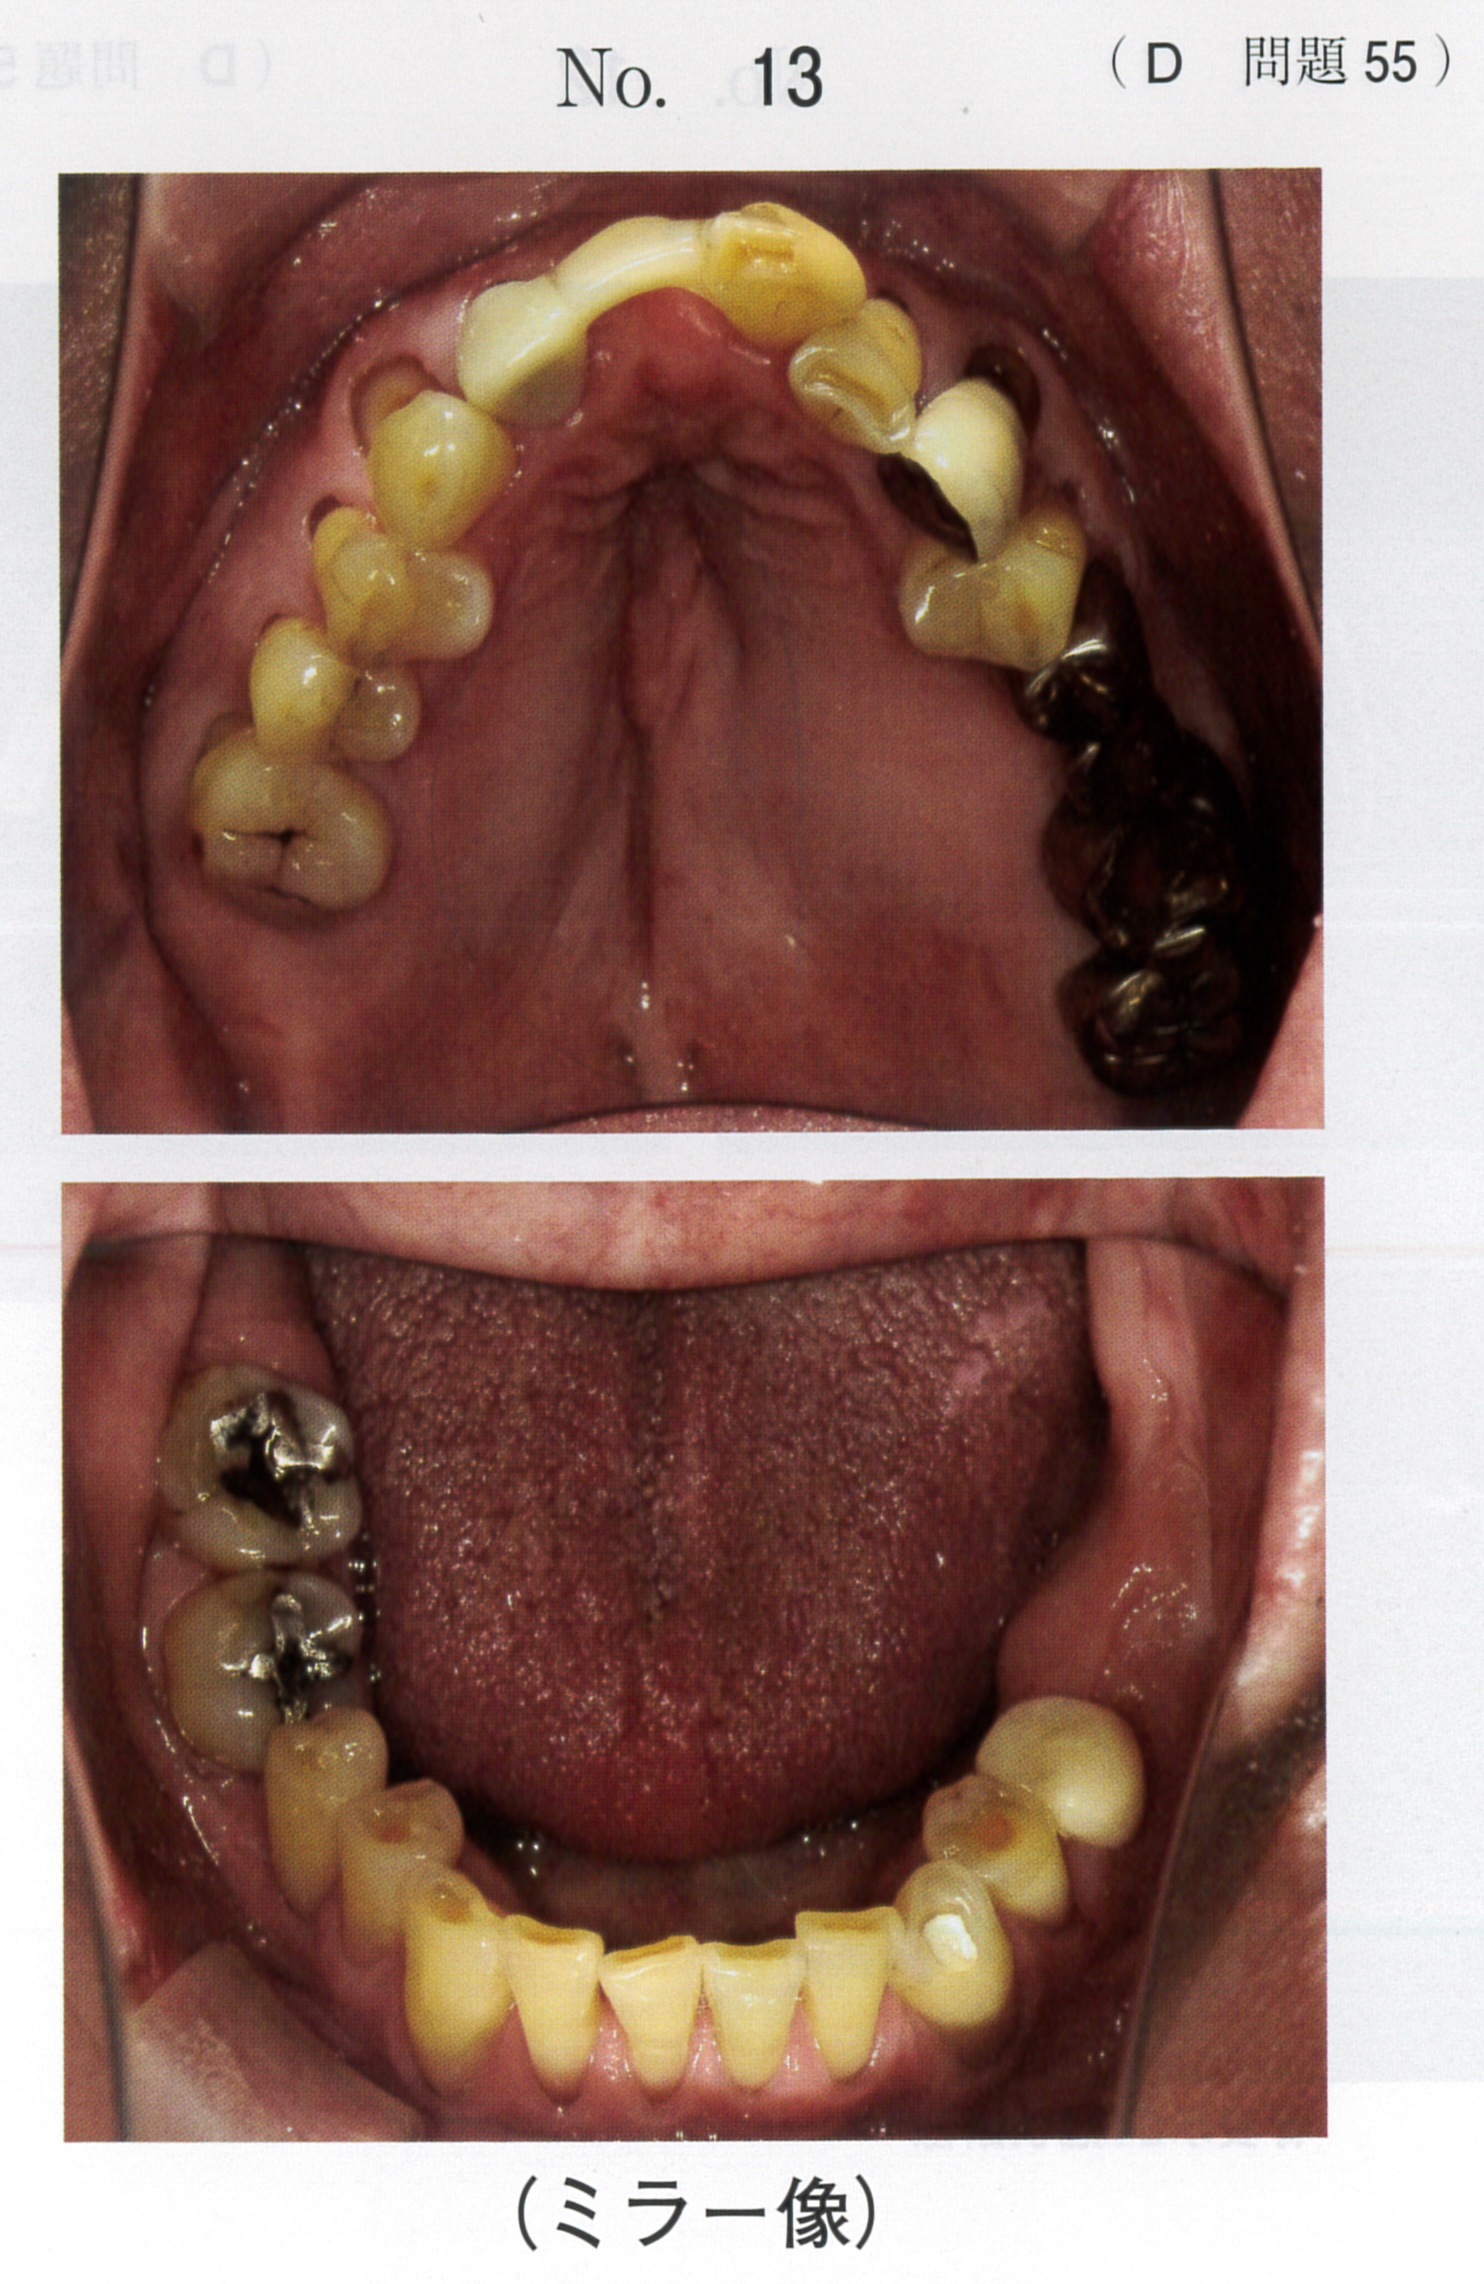

臨床医学に特化した国試対策テキスト。DES本校生限定資料 ① 小児歯科学(総括)P25② 臨床実技関連テキストP31③ 国試に出る症候群まとめP25状態)一切書き込み無し。裁断済み(神経質な方は控えてください)その他)ペット喫煙無し差し替え防止のため、返品返金不可。バラ売りの場合は、1冊子5000円とします。セット価格にしておきます。- タイトル: 国試に出る名詞整理まとめ- 内容: 臨床医学に関するテキストと資料- 形式: 印刷物- ページ数: 複数ページ- 対象: 医療従事者向け- 言語: 日本語ご覧いただきありがとうございます。